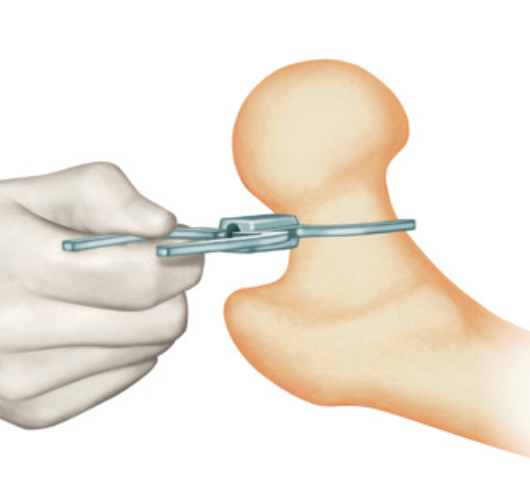

Technique

Techniques

Birmingham Resurfacing

Smith&Nephew Birmingham Resurfacing PDF

Avoid

- notching

- varus

- open acetabulum

Technical issues

Oversized head

Varus Femoral Component

Femoral head notching

Open Acetabular Component - may cause point loading and increased metal wear